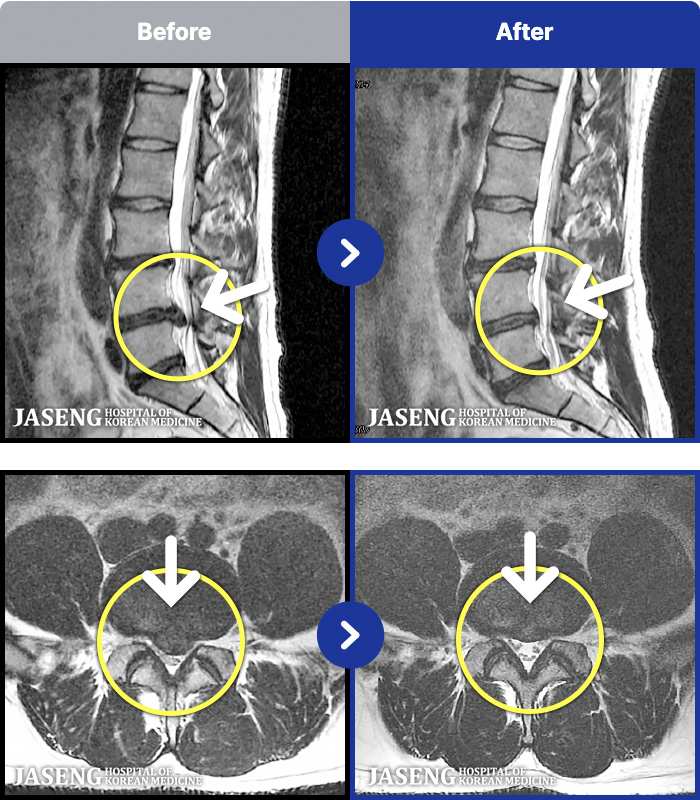

MRI ġ

88 MRI ũ ʸ Ȯϼ.

Ƹ ϰ ־.

[õ] 25.03.18~25.07.22

ȯںп Ǹ ǿ ԿǾ, ο ġ ۿ Ƿ ġḦ Ͻñ ٶϴ.